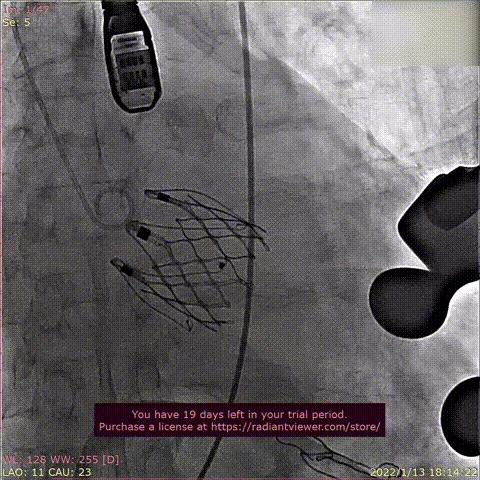

瓣膜释放过程

球囊域扩张

球囊后扩张